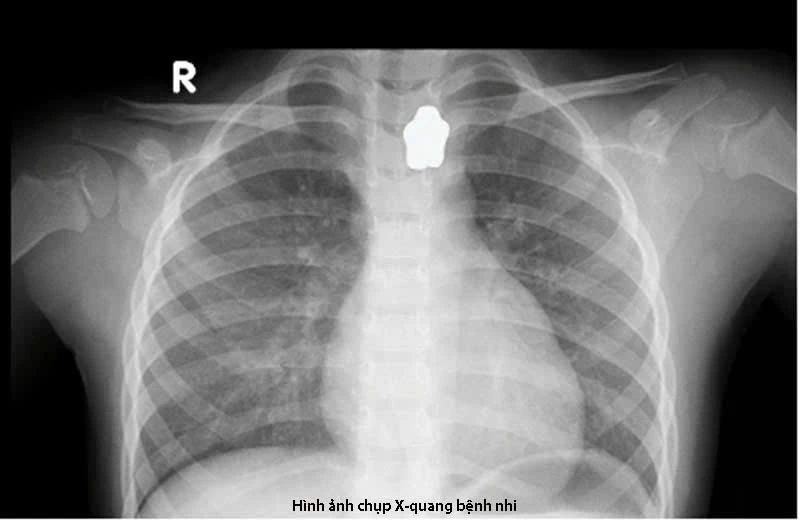

Cụ thể, 18 giờ ngày 14-4, bệnh nhi nhập viện với triệu chứng mắc nghẹn, đau vùng cổ và khó thở nhẹ.

Ngay sau khi chụp X-quang phát hiện dị vật cản quang vùng cổ, các bác sĩ đã nhanh chóng tiến hành nội soi gắp dị vật thành công.

Bé gái nuốt nam châm và dị vật cản quang vùng cổ. Ảnh: BVCC

“Với trường hợp bệnh nhi này, dị vật có bề mặt trơn láng và mắc tại thực quản trên, chiếm toàn bộ lòng thực quản của bé. Các bác sĩ đã thực hiện phương án theo nhu động thực quản đẩy dị vật xuống lòng dạ dày, sau đó dùng vợt để lấy dị vật ra ngoài”, bác sĩ Chương thông tin.